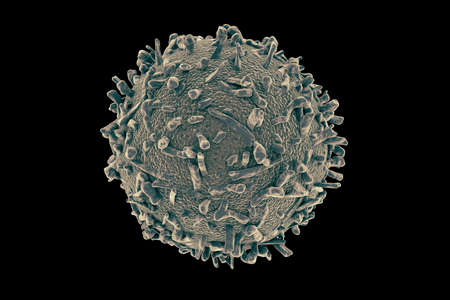

White blood cells (WBCs), also called leukocytes or leucocytes, are the cells of the immune system that are involved in protecting the body against both infectious disease and foreign invaders. (WIkipedia)